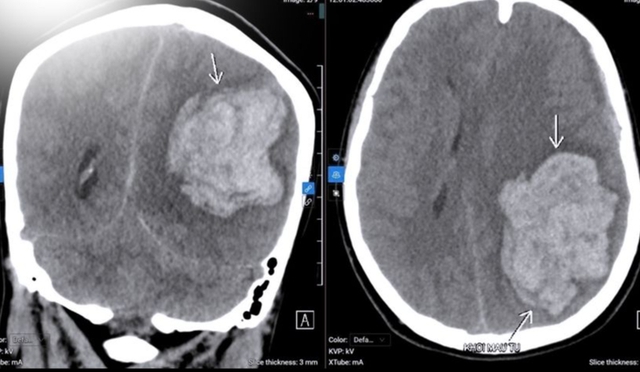

Kết quả chụp CT có khối máu tụ nội sọ cấp tính kích thước lớn tại bán cầu trái (khoảng 78×58,5×57 mm). Tình trạng phù não lan rộng làm lệch đường giữa sang phải 14 mm và chèn ép lều tiểu não trái.

Hình ảnh ổ xuất huyết nhu mô não bán cầu trái trên CT sọ não của người bệnh. Ảnh: BVCC

Ghi nhận thoát vị thái dương trong, gây đè ép thân não, một nhánh tĩnh mạch giãn sát bờ sau khối máu tụ, ổ phình khoảng 2 mm, nghi ngờ mạch máu dị dạng. Lớp máu dưới màng cứng bán cầu trái dày khoảng 7,5 mm. Nguyên nhân chảy máu từ khối dị dạng mạch não.